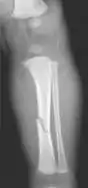

The material factual allegations of the amended complaint are as follows. Plaintiff was born on May 14, 1970. On repeated occasions during the first year of her life she was severely beaten by her mother and the latter's common law husband, one Reyes. On April 26, 1971, when the plaintiff was eleven months old, her mother took her to the San Jose Hospital for examination, diagnosis, and treatment. The attending physician was defendant Dr. Flood, acting on his own behalf and as agent of the defendant San Jose Hospital. At the time, the plaintiff was suffering from a comminuted spiral fracture of the right tibia and fibula, which gave the appearance of having been caused by a twisting force. Plaintiff's mother had no explanation for this injury. Plaintiff had bruises over her entire body. In addition, she had a non-depressed linear skull fracture which was then in the process of healing. Plaintiff demonstrated fear and apprehension when approached. Inasmuch as all plaintiff's injuries gave the appearance of having been intentionally inflicted by other persons, she exhibited the medical condition known as the battered child syndrome.

It is alleged that proper diagnosis of plaintiff's condition would have included taking X-rays of her entire skeletal structure, and that such procedure would have revealed the fracture of her skull. Defendants negligently failed to take such X-rays, and thereby negligently failed to diagnose her true condition. It is further alleged that proper medical treatment of plaintiff's battered child syndrome would have included reporting her injuries to local law enforcement authorities or juvenile probation department. Such a report would have resulted in an investigation by the concerned agencies, followed by a placement of plaintiff in protective custody until her safety was assured. Defendants negligently failed to make such report.

For example, the leading article by Kempe et al., op. cit., supra,[11] states that "A physician needs to have a high initial level of suspicion of the diagnosis of the battered-child syndrome in instances of subdural hematoma, multiple unexplained fractures at different stages of healing, failure to thrive, when soft tissue swelling or skin bruising are present, or in any other situation where the degree and type of injury is at variance with the history given regarding its occurrence . . . ." (Id., at p. 20.) Of the different types of fractures exhibited, an arm or leg fracture caused by a twisting force is particularly significant because "The extremities are the 'handles' for rough handling" of the child by adults. (Id., at p. 22.) The article also contains numerous recommendations to conduct a "radiologic examination of the entire skeleton" for the purpose of confirming the diagnosis, explaining that "To the informed physician, the bones tell a story the child is too young or too frightened to tell." (Id., at p. 18.) Finally, on the subject of management of the case it is repeatedly emphasized that the physician "should report possible willful trauma to the police department or any special children's protective service that operates in his community" (id., at p. 23) in order to forestall further injury to the child: "All too often, despite the apparent cooperativeness of the parents and their apparent desire to have the child with them, the child returns to his home only to be assaulted again and suffer permanent brain damage or death." (Id., at p. 24.)